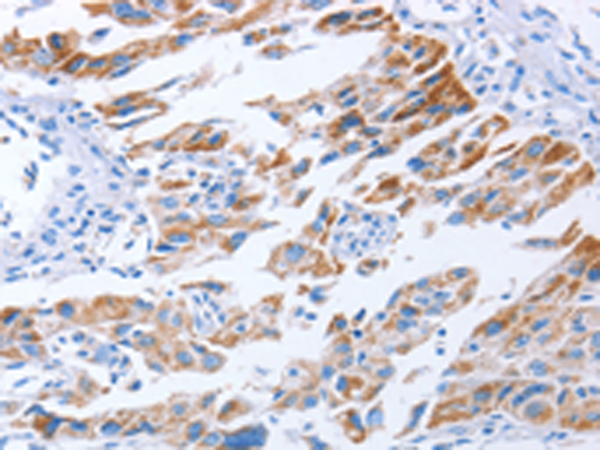

分类: 科研抗体货号: P07409别名: ARM1; EMSP; PSTS; AI2A1; EMSP1; KLK-L1; PRSS17; kallikrein应用: IHC反应种属: Human